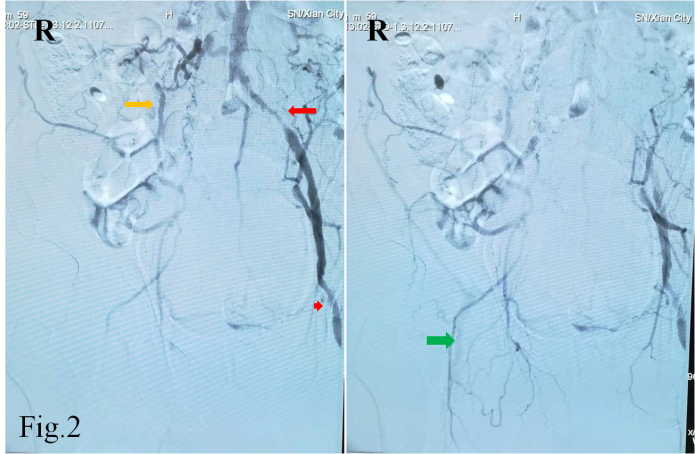

55岁的白先生因急性脑梗死入住男同视频 神经内科,双侧颈部血管、锁骨上窝均可闻及血管杂音,为详细评估脑血管情况,拟行全脑血管造影检查。常规的脑血管造影检查首选右侧股动脉穿刺入路完成造影,但是该患者存在明确的右下肢间歇性跛行病史,双侧股动脉搏动触摸不到。下肢动脉超声提示双侧股动脉中度狭窄,股动脉、腘动脉等下肢血管动脉粥样硬化斑块形成。仔细评估后,考虑无法从股动脉穿刺进行造影检查。经神经介入医生周密准备,拟进行经右侧桡动脉穿刺完成脑血管造影及下肢血管造影检查。

经过导丝引导下,谨慎地将造影导管置于主动脉弓,造影显示Ⅱ型主动脉弓,介入医生顿感压力倍增。常规路径下(股动脉置管),Ⅱ型主动脉弓要比Ⅰ型主动脉弓操作难度复杂的多,颈部血管从主动脉弓发出角度、走形、迂曲度及造影导管在主动脉弓如何塑形、塑形成功率等等都会制约操作时间、顺畅性,稍有不慎可能导致主动脉弓斑块脱落、主动脉动脉夹层等情况发生。增加了在经桡动脉在Ⅱ型主动脉弓上超选造影的难度。经介入医生耐心、细致操作下,反复尝试降主动脉造影导管成型,逐步“逆行”完成全脑血管造影及下肢动脉造影。

常规脑血管造影检查经股动脉穿刺术后患者需要卧床、下肢制动24小时。经上肢桡动脉穿刺,术后患肢无需严格制动,也无需严格卧床,可避免患者长时间卧床后腰酸背痛及在床上排便的烦恼。男同视频 开展经桡动脉行全脑血管造影术,为后期复杂血管内治疗奠定技术基础,也为男同视频 卒中中心建设丰富技术手段。